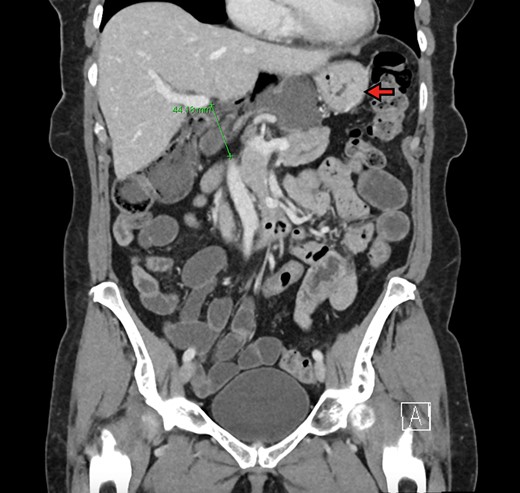

The patient is a 70-year-old woman who presented to the emergency department with acute-onset abdominal pain throughout her epigastrium for approximately 2 hours. The pain was constant and severe, extending across the bilateral upper quadrants. She had experienced pain like this once before within the past year which spontaneously resolved within 4 hours. The patient’s last oral intake was an hour before onset of the pain, and she denied any fevers, chills, nausea or vomiting. She was an otherwise healthy woman who took no medications and had no abdominal surgical history. On admission, vital signs were normal, with a heart rate in the 70’s. Although initially reported as tender by emergency department staff, after pain medication and intravenous fluids, examination by the surgical team revealed resolution of pain and a soft, non-tender abdomen. Lactic acid on presentation was 5.0 mmol/l, and her white blood cell count was 9600 µl−1, with the remainder of her laboratory values within normal limits. She underwent a computed tomography scan which demonstrated herniation of her cecum through the FoW, causing compression of the inferior vena cava (IVC) and portal vein (Figures 1–3).

The cecum is absent from the right lower quadrant and is located between the liver and stomach (red arrow) visualized as an air-fluid level (green arrow). Compression of the portal vein by herniated contents is demonstrated (blue arrow).

Coronal view demonstrating FoW measurement and herniated contents. The stomach is demonstrated by the red arrow. The FoW is shown to be dilated at 4.4 cm.